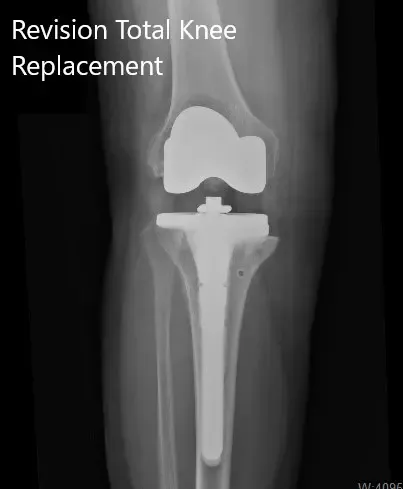

Radiografía postoperatoria que muestra las vistas lateral y anteroposterior de la rodilla derecha.

IMPLANTE UTILIZADO: Componente tibial tamaño 2 con extensión del tallo de 13 mm x 100 mm de longitud y talla 2. Aumento medial de 5 mm con polietileno flexible de 17 mm con rótula de 32 mm, espesor B,5 mm, con componente femoral flexible tamaño C.